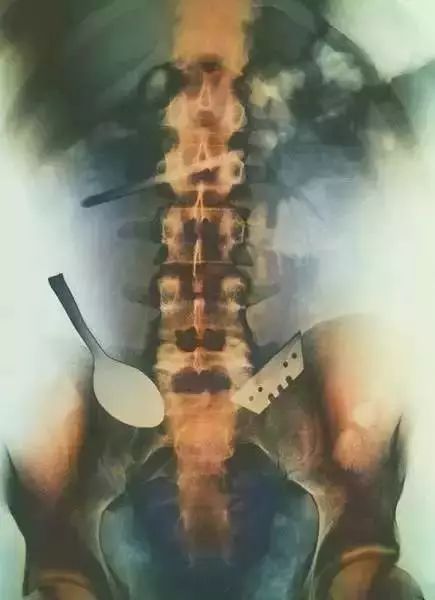

2、这张有色的X光片的主人,他的肠道里有一个勺子和一个刀片。